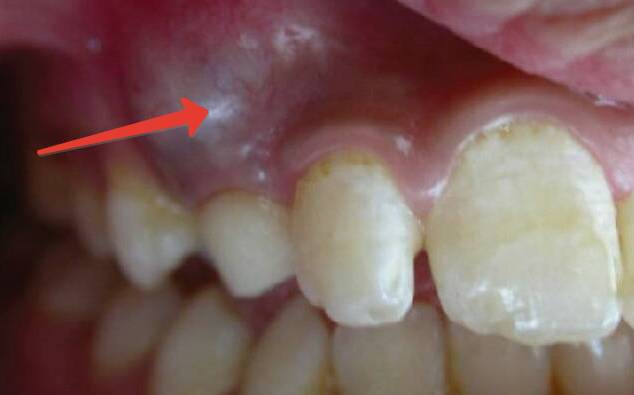

Как выглядит киста на зубе? Фото и рентген

Невооруженным глазом неопытному человеку обнаружить кисту сложно. Когда же ее становится визуально заметно, это значит, что она уже на завершающем этапе своего развития, имеет очень большие размеры, а боль от нее становится нетерпимой, резкой и заметной.

Десна в этом месте может заметно покраснеть, выделяться цветом от здоровых зон, значительно опухнуть. Воспалительная киста может выглядеть бледно желтой или серой, с красным ободком на краях.

Для стоматологов главным способом диагностики остается рентгеновский снимок, на нем зубная киста имеет форму кругловатого темного пятна разных размеров, в зависимости от стадии и протекания болезни. Располагается это пятно у зубного корня, в его высшей точке и имеет довольно четкие контуры.